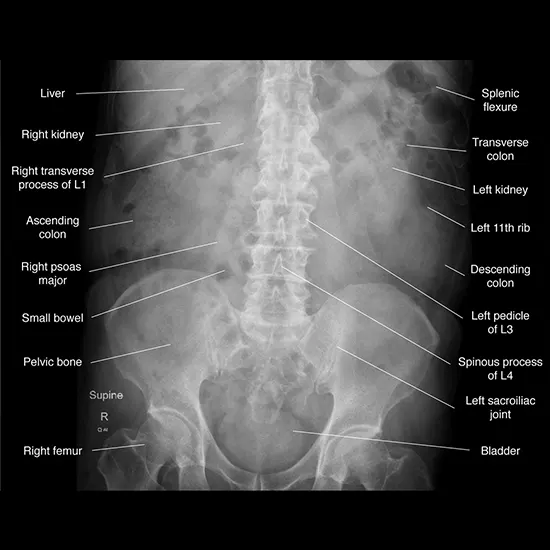

In the abdomen, x-rays can be used to assist diagnose a vary of stipulations affecting the digestive tract, urinary system, reproductive organs, and different structures. For example, x-rays can realize the presence of kidney stones, gallstones, or different kinds of blockages in the urinary or digestive system.

They can additionally be used to consider the measurement and function of organs such as the liver, spleen, and pancreas, and to pick out abnormalities such as tumors, cysts, or abscesses.